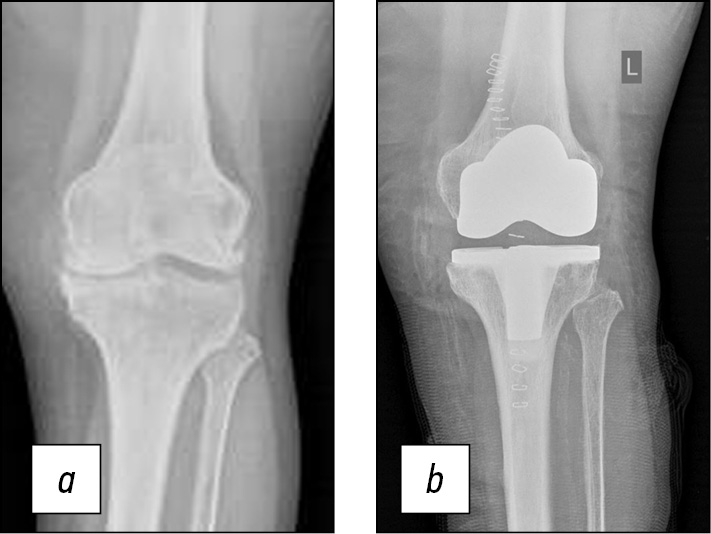

Последующие этапы, подготавливающие уже непосредственно к установке компонентов эндопротеза коленного сустава, выполняются штатно, в том числе с последующей оценкой балансировки сгибательного и разгибательного промежутков, проверкой запланированных ранее размеров на примерочных компонентах эндопротеза. Затем выполняется уже финальная установка компонентов эндопротеза коленного сустава. В данном случае размеры полностью совпали с предоперационным планом (бедренный компонент Zimmer, размер D, плато большеберцовой кости № 3) (рис. 10). Рана послойно ушита, выполнены контрольные рентгеновские снимки в прямой и боковой проекциях (рис. 11, 12).

Рис. 11. Рентгенограммы больной Т. в прямой проекции: а — до оперативного лечения, b — после оперативного лечения.

Fig. 11. Radiographs of patient T. in frontal projection: a — before surgical treatment, b — after surgical treatment.